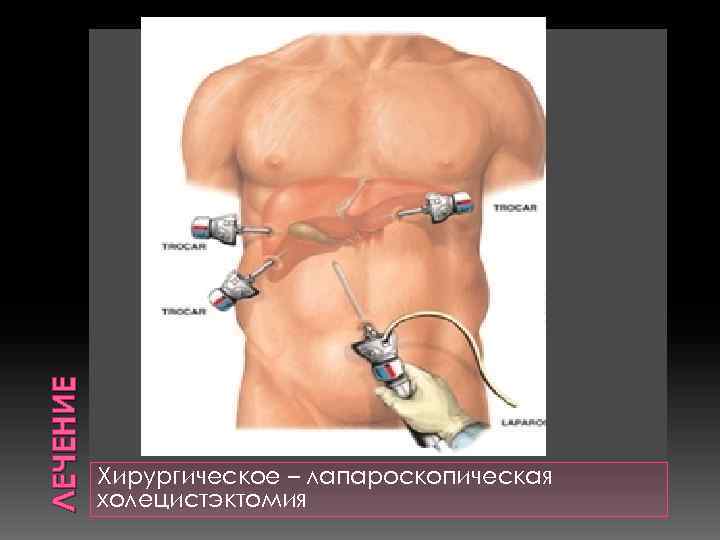

ЛЕЧЕНИЕ Хирургическое – лапароскопическая холецистэктомия

ЛЕЧЕНИЕ Хирургическое – лапароскопическая холецистэктомия